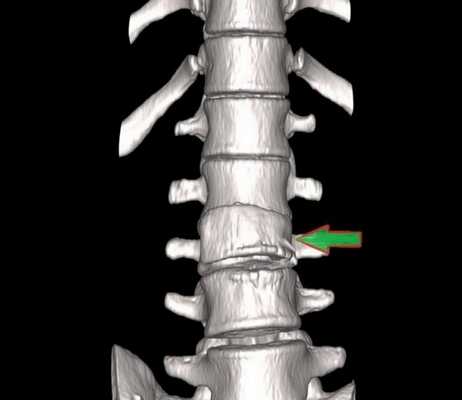

Перелом грудного отдела (трехмерная и сагиттальная проекции)

Компрессионный перелом (показан стрелкой) поясничного отдела позвоночника